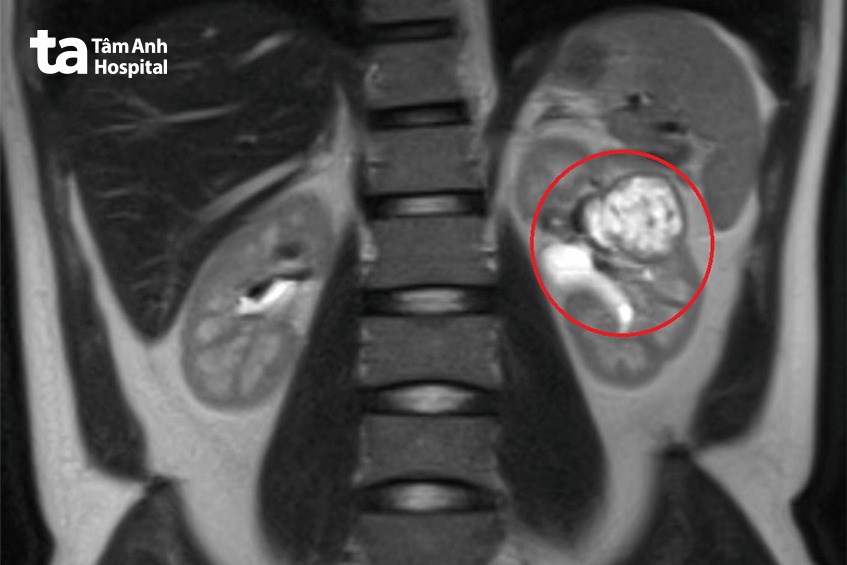

Anh T.T.L. (35 tuổi, ngụ TP.HCM) phải cắt toàn bộ thận trái do ung thư thận. Tiến sĩ bác sĩ Nguyễn Hoàng Đức, Trưởng khoa Tiết niệu, Trung tâm Tiết niệu – Thận học – Nam khoa, cho biết người bệnh không khám sức khỏe định kỳ thường xuyên, khi phát hiện khối u đã 4,5cm, lại nằm sát vùng xoang thận dính với các mạch máu chính của thận. Các xét nghiệm chẩn đoán hình ảnh CT-scan và MRI cho thấy đầy đủ các đặc điểm điển hình của u thận ác tính.

Vì khối u lớn lại ở vị trí “hiểm”, nếu phẫu thuật giữ lại phần thận khỏe mạnh thì vẫn có nguy cơ bỏ sót tế bào ung thư; và về mặt kỹ thuật không tái tạo lại được hình thái của phần thận còn lại; do đó buộc ê kíp phải phẫu thuật nội soi cắt toàn bộ thận trái.